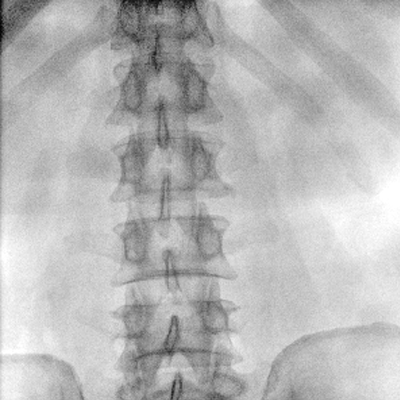

動(dòng)態(tài)板C形臂 開(kāi)啟清晰影像新篇章 PLX118F

臨床適用科室:骨科、普通外科、矯形外科、創(chuàng)傷外科、泌尿外科、脊柱外科、疼痛外科、消化科、婦科等科室。

大尺寸動(dòng)態(tài)平板探測(cè)器,高DQE、低噪聲、圖像清晰。采用多分辨率圖像增強(qiáng)處理技術(shù),不同部位不同圖像處理算法,滿足客戶多樣化的需求。

采用智能變頻脈沖透視技術(shù),優(yōu)化圖像質(zhì)量的同時(shí)降低輻射劑量,呵護(hù)醫(yī)患健康